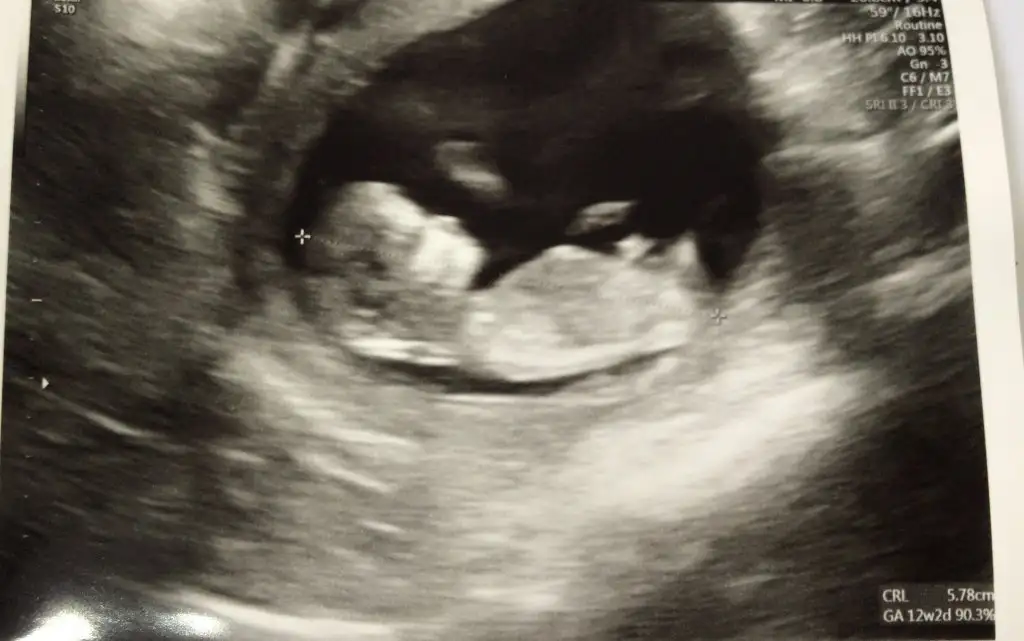

Kız gibi ne oldu cinsiyet belli oldu muEki Görüntüle 2812079 Merhaba tahmin de bulunurmusunuz benim için de karından usg

Ramzi teorisine göre cinsiyet tahmini yapacagim ilk ultrasyon resminizi atin bakiyim. Eger cinsiyetiniz belliyse hic söylemeeyin bakalm dogru tahmin edebilecekmiyim daha dogrusu ramzi teorisi hakli cikacak mi?

Yorumlayabilir misiniz ?Merhaba millet

Tatlim karindansa muayene erkek cinsiyeti çok eminim vajinal muayeneyse kiz çok belli ultrason ..cinsiyeti öğrenince yazar misinYorumlayabilir misiniz ?

Tatlim karindansa muayene erkek cinsiyeti çok eminim vajinal muayeneyse kiz çok belli ultrason ..cinsiyeti öğrenince yazar misin